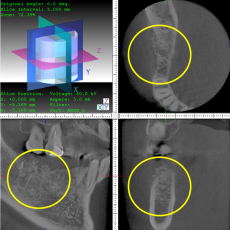

骨再生

骨再生した箇所にインプラントを埋入します。

CTで治療計画を綿密に練ったうえで行いました。

インプラント埋入後のレントゲン画像です。